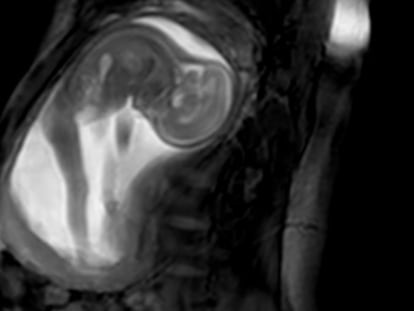

Dar a luz es uno de los momentos más emocionantes en la vida de una mujer. El dolor, el cansancio, el miedo y la felicidad se pueden conjugar en un solo instante. Fotografiarlo se ha convertido en un arte que todos los años se premia. Estas son las mejores de 2017